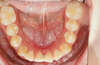

Béance traitée par gouttières

Début du traitement